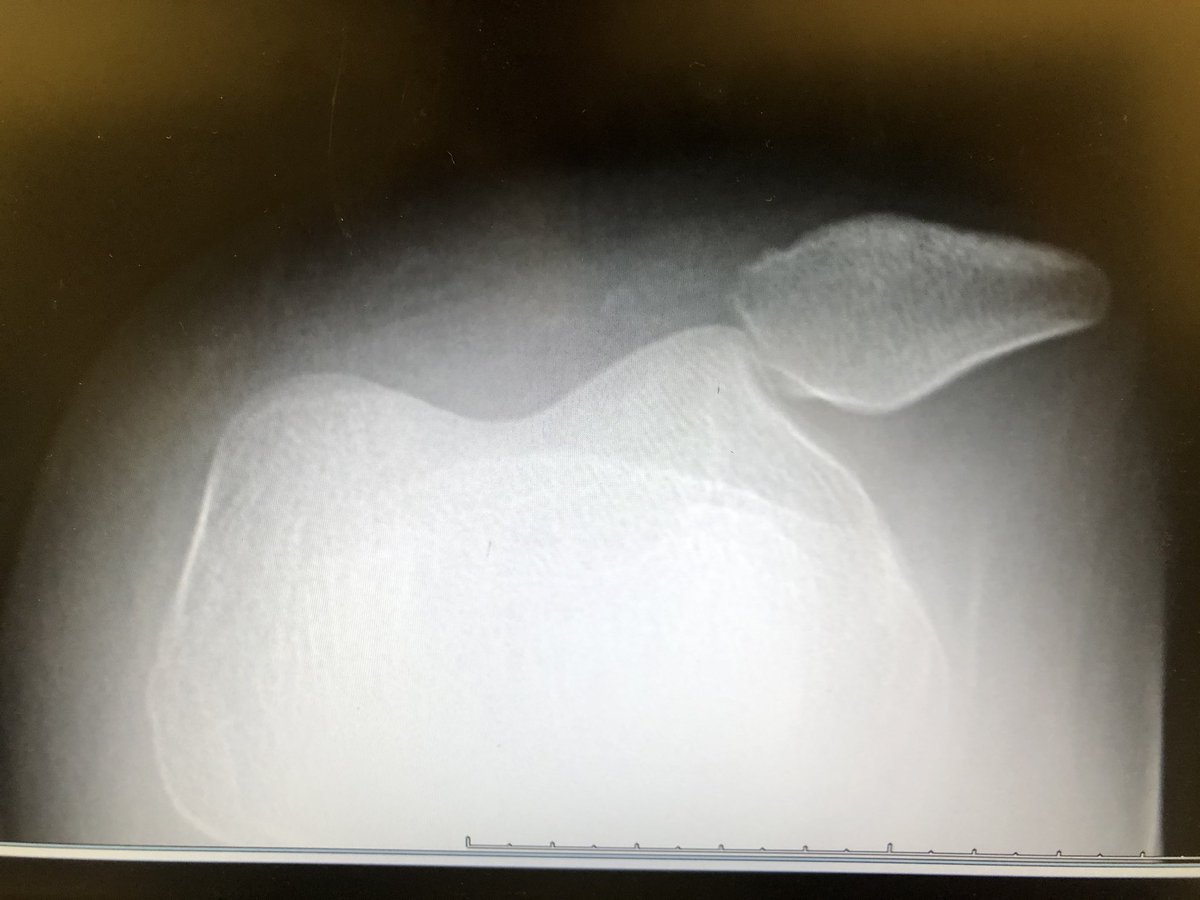

HB 3459 in the #txlege represents an important opportunity to decrease the prior authorization burden. Thanks to @DrGregBonnen @SenJaneNelson @DrBuckinghamTX for supporting this important concept. @TSAOG_Ortho takes a look at prior auth in the San Antonio area in this graphic.